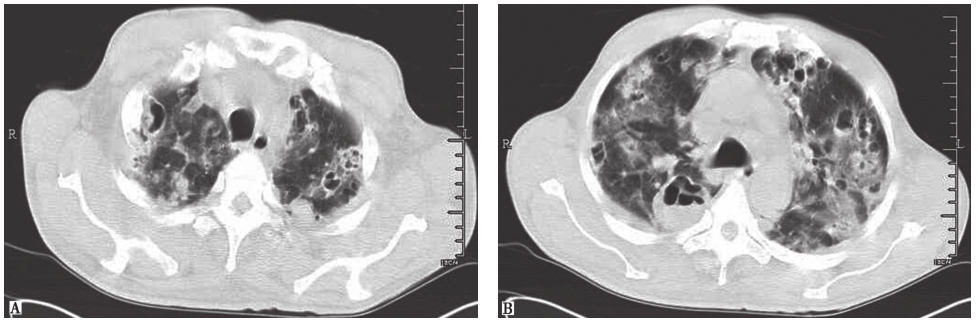

图4弥漫性肺泡出血胸部CT表现

女性患者,48岁,因咳嗽2个月、发热4天入院。起病时胸部CT表现为两肺多发结节(A),之后出现两肺弥漫性肺泡出血,部分病变有游走性改变(B)。诊断为弥漫性肺泡出血

图5肺鳞癌胸部CT表现

男性患者,63岁,痰中带血1个月。胸部CT发现左上肺空洞性病变,病理诊断为肺鳞癌